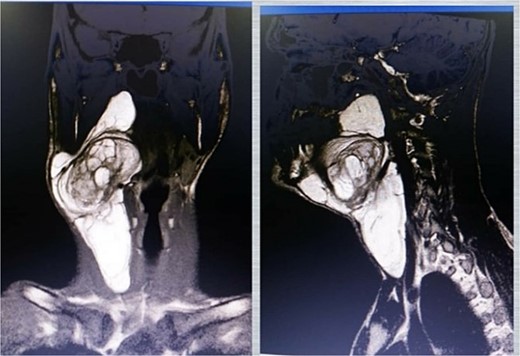

A neck ultrasound revealed a well-defined, solid, mildly hyper-echoic, heterogeneous subcutaneous mass located on the right side of the neck. A contrast-enhanced MRI scan showed a 14 cm diameter, well-demarcated, high-signal, non-homogeneous mass adjacent to the carotid artery and thyroid gland (Figs 1 and 2). The radiologist suggested lipoma as the most probable diagnosis. Ultrasound-guided fine-needle aspiration (FNA) of the mass identified some lipocytes and fibrocytes but no malignant cells.

MRI images showing a high-signal mass on both T1 (left) and T2 (right) sequences.